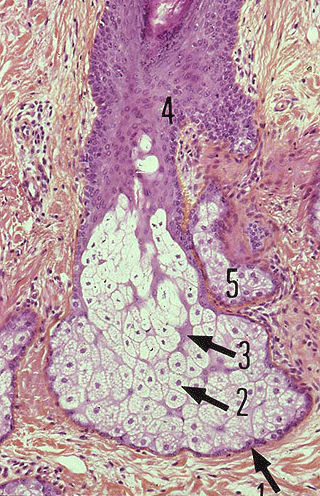

Glande sébacée Les glandes sébacées sont formées d'une couche germinative (1), cellules aplaties identiques aux cellules de la zone germinative de l'épiderme ( infos).

La couche germinative est plaquée contre une membrane basale, elle-même insérée dans une sorte de capsule formée par du tissu conjonctif dense.

Elle fabrique les cellules sécrétrices (2) et les formations cloisonnantes non sécrétrices (3).

Plus on approche du centre de la glande, plus les cellules sont chargées de corps gras qui finit par les désintégrer ( infos). Il peut y avoir ou non de canal central formé par destruction cellulaire.

Les glandes sébacées sont des glandes exocrines de type holocrine ( infos).

Les glandes sébacées sont des glandes alvéolaires ( infos) simples ou composées en un ou plusieurs acinus ( infos).